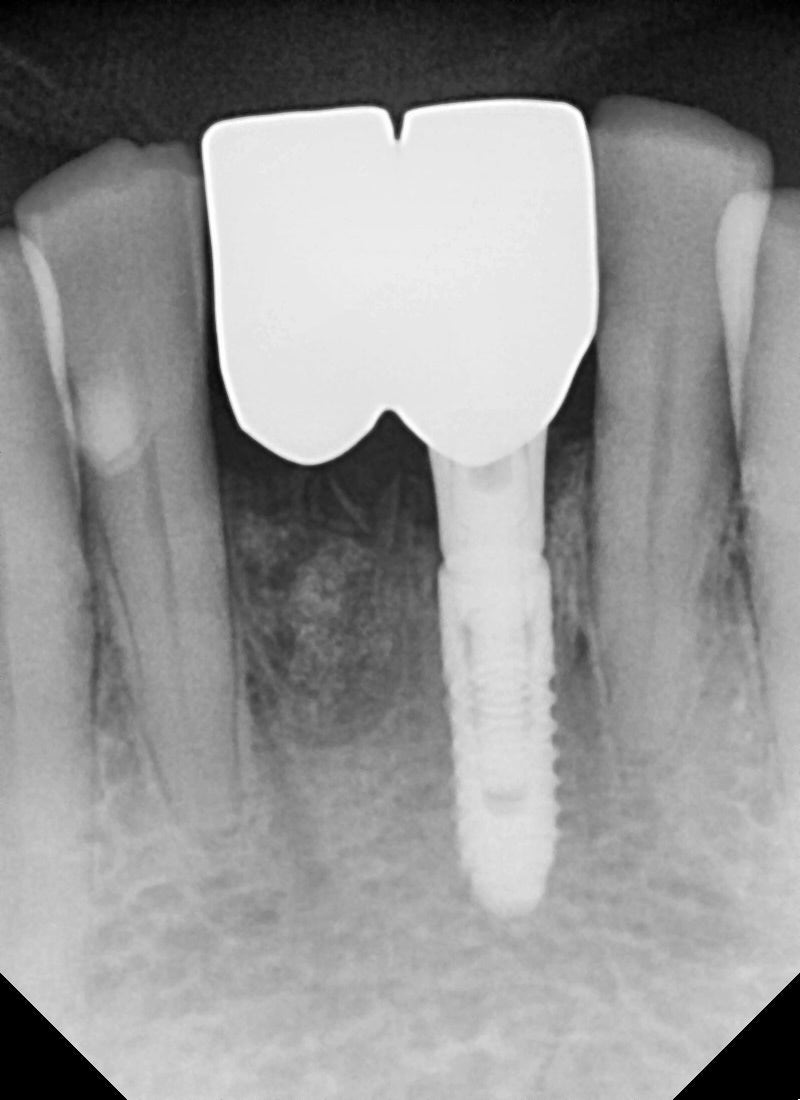

수술 후 최종 보철까지 완성 소요 시간

수술 후 최종 보철물까지 3달 정도가 소요되었습니다.

치조골이식부위도 볼륨이 잘 유지 되어있고

보철물 라인도 자연스럽게 제작되었습니다

임시치아 때보다 색상은 주변 치아와 맞춰졌고

수술후 붓기가 가라앉은 잇몸에

맞춰 치아 형태도 제작이 되었습니다.

웃을 때 말할 때 가장 잘 보이는 앞니 부분이기 때문에

지내시면서 환자분 요구에 맞춰서 몇 번의 수정을 해서

환자분께서 최종적으로 오케이를 해주셔서

최종 부착을 마무리했습니다.